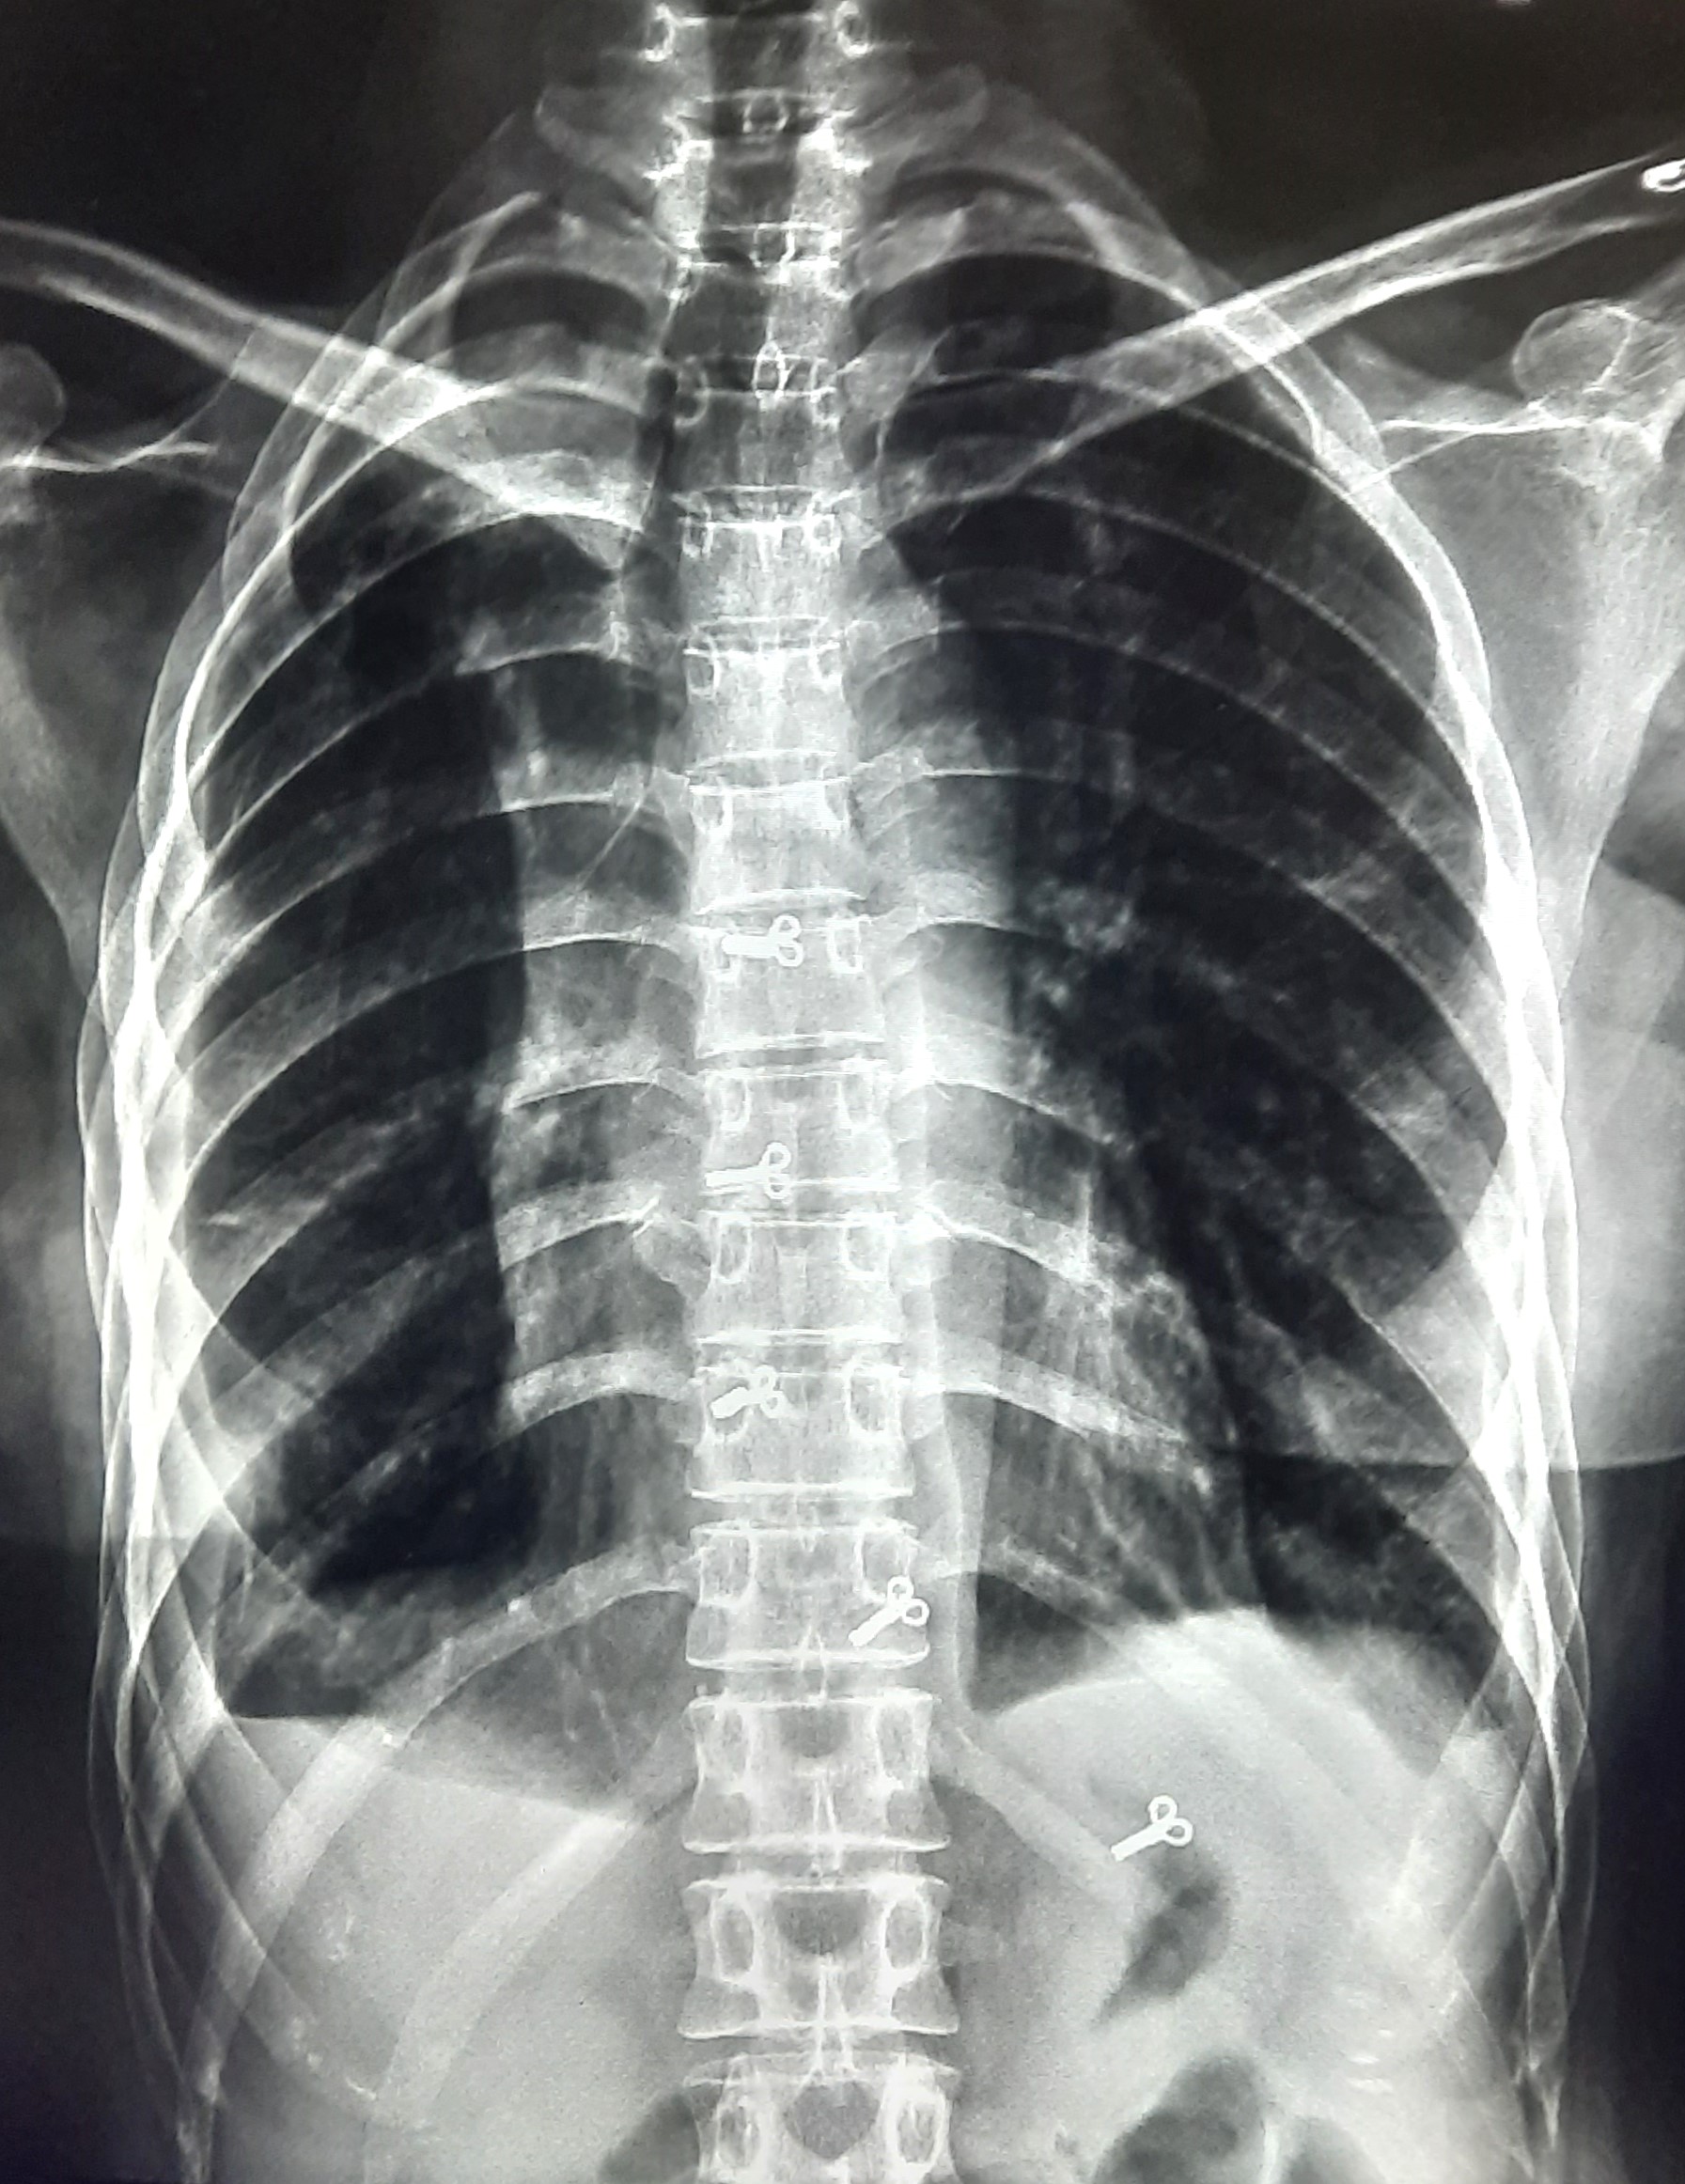

| 283 | IGGMC, Nagpur, Nagpur | P2 | 29-4189 Follow-up of 29-3923 |

Monali Pralhad Milmile | Consent taken on Paper | 46 Yrs. |

Provisional Diag : PTB Follow-up

Final Diag : Pleural Effusion |

TB Case (Confirmed) | Right Sided Upper Zone Fibrotic Lesion, Tracheal Pull Left side, Right sided & Left Sided Pleural Thickening Present, Right sided & Left Sided CP Angle Blunting Present, | Abnormality visible on x-ray |